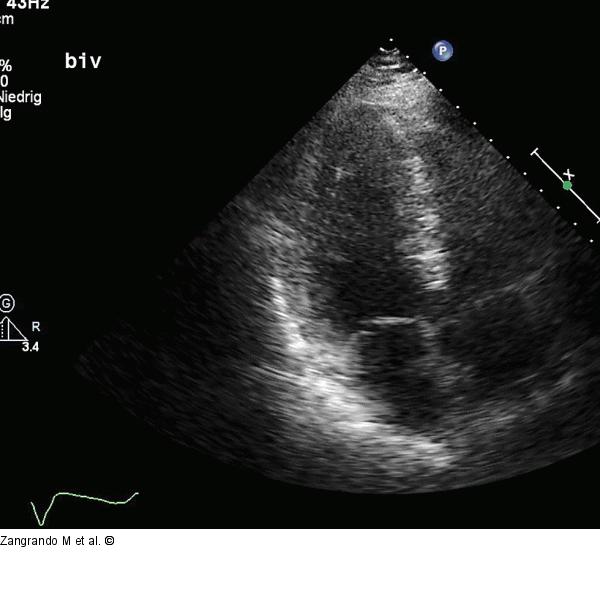

Abbildung 8: Echokardiographie - Film 4 Echokardiographischer Dreikammerblick (gleiche Untersuchung wie Film 3). |

Echokardiographischer Dreikammerblick (gleiche Untersuchung wie Film 3). |